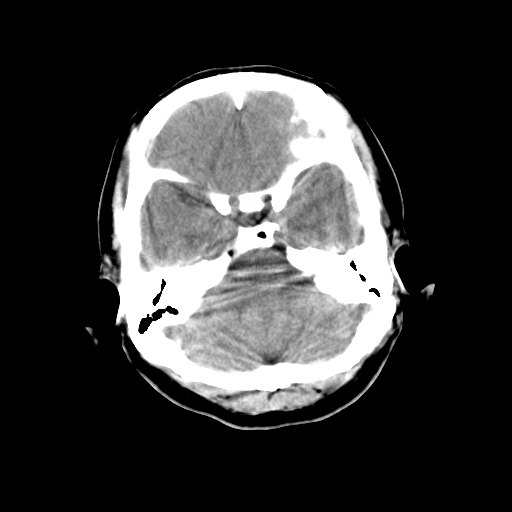

标题: CT23995:女,42岁,前额部外伤1小时,伤后头痛。 [打印本页]

女,42岁,前额部外伤1小时,伤后头痛。

颅内未见明显异常,枕骨松质骨瘤可能性大。颅骨板障起源骨瘤较常见,骨血管瘤有垂直骨针及粗大钙化,嗜酸性肉芽肿软组织有改变,典型者可见“纽扣状”死骨,年龄通常较小。

左枕骨松质骨不均匀低密度灶,边缘清楚,考虑良性松质骨性骨瘤可能性大。